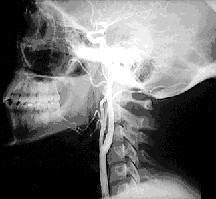

A 65-year-old man presented in his physician's office complaining of frequent headaches focused primarily on the right side and a series of four episodes of transient dysfunction involving the left side of his body during the last two months. These episodes involved progressive symptoms, beginning with only numbness in his left hand during the first episode, muscle weakness in his left arm and left leg during the second and third episodes, and limb weakness accompanied by slurred speech during the fourth episode. Auscultation of the neck indicated a bruit present on the right side. An arteriogramrevealed ulcerated stenosis of the right carotid bifurcation and mild left-sided carotid stenosis. The patient was advised that he should undergo a carotid endarterectomy immediately in order to prevent an otherwise imminent stroke. The patient submitted to the surgery, which was performed without incident, and has experienced no further headaches or episodes of left-sided dysfunction.

In this context, a bruit is a systolic murmur heard only in the neck. It is caused by turbulent and noisy blood flow over a roughened surface (i.e. an atherosclerotic plaque).- What is an arteriogram and how is it obtained?

An arteriogram is a radiograph demonstrating the course and lumen diameter of an artery and its tree. Arteriograms are obtained via x-ray imaging after a injection of a radiopaque contrast medium into the arterial tree.- What is an endarterectomy?

The most common location for atherosclerotic plaque formation is at the bifurcation or branch points of arteries, in the case of the carotid arteries it is at the carotid bifurcation.References: